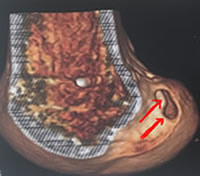

Radio post-opératoire

La radio post-opératoire montre le petit endobutton métallique sur le fémur (non résorbable).